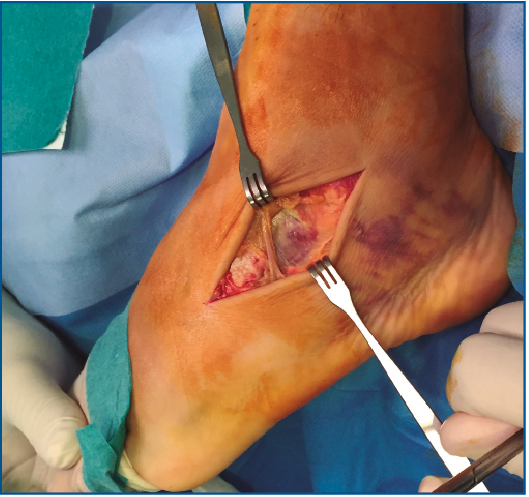

Es intervenido a la semana de la lesión realizándose, bajo anestesia raquídea e isquemia del miembro, una incisión dorsolateral desde la articulación calcaneocuboidea hasta la base del 4.º MTT. Se expuso el cuboides reflejando el extensor corto a dorsal y peroneo corto a plantar y se evidenció la desalineación del cuboides con el 4.º y 5.º MTT y el calcáneo creada por la luxación. Se realizó una reducción manual del mismo y una fijación con 2 agujas de Kirschner (agujas K) metatarsocuboideas, 1 aguja cuboideocalcánea y 1 calcaneocuboidea, realizándose al mismo tiempo una fijación de la apófisis lateral del astrágalo con un tornillo canulado (Figuras 3, 4 y 5). Se mantuvo 6 semanas inmovilizado, momento en el que se retiraron las agujas K. A la 6.ª semana, se inicia la carga con ortesis de carga hasta la 8.ª semana.

Figura 3. Abordaje quirúrgico longitudinal dorsal sobre el 4.º radio. Exposición del músculo extensor corto de los dedos.